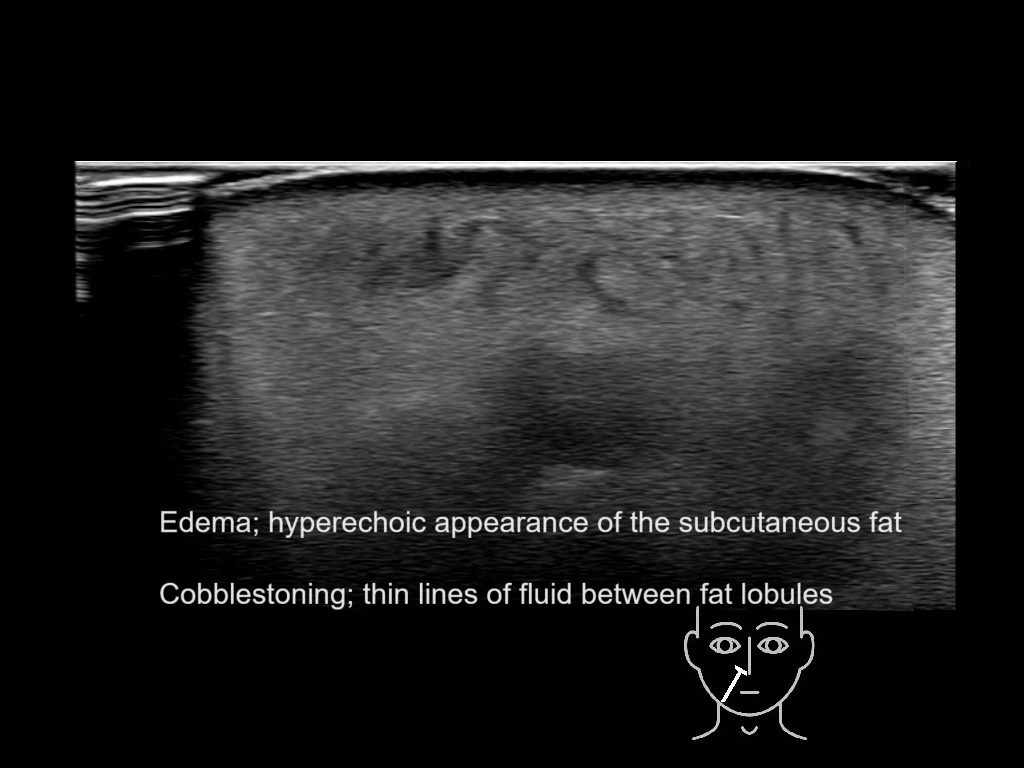

With ultrasound signs of inflammation can be visualized. Edema can be seen as a hyperechoic appearance of the subcutaneous fat, sometimes separated by hypoechoic fluid filled area’s, known as cobblestone appearance. Increased vascularization (hypervascularity) can be seen on colour Doppler. An abscess will appear as a fluid collection appearing as an irregular hypoechoic area with heterogeneous internal echoes and a thickened wall. Posterior acoustic enhancement can be present, and there is vascularity around but not within the mass. Under ultrasound guidance, abscesses can be managed by needle aspirations (18G) under antibiotic cover.

Study the first image to recognize the different layers. If you are sure about the layers, swipe to the second image to view the answer (if applicable).